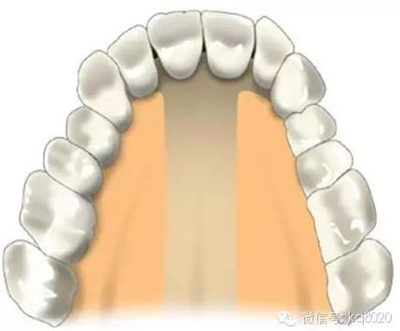

根據(jù)骨類型,骨密度,牙根間距、粘膜厚度不同,把上下頜分為不同區(qū)域,分別用紫橙藍黃四種顏色標記,這些區(qū)域就是傳統(tǒng)的可植入部位,每個部位所選擇的支抗釘也相應會有所差異